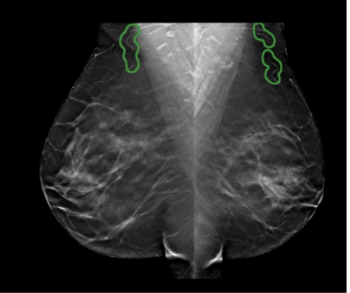

Utilized in conjunction with screening digital mammography or digital breast tomosynthesis (DBT), the artificial intelligence (AI)-powered software cmAngio may help detect and localize breast arterial calcification (BAC), an incidental finding that has been linked to an elevated risk for heart disease and stroke.